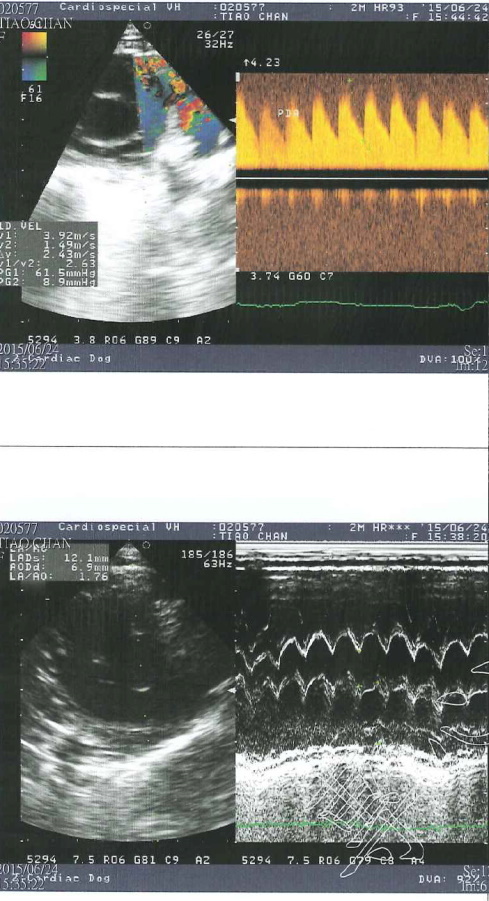

而幸運長大的三隻小奶貓分別取名貂蟬、圓圓、西施,而六月天氣變化大,早上大太陽夜裡又滂沱大雨,小貓們出現鼻氣管炎的現象,張口呼吸感覺很不舒服,貂蟬由其嚴重,呼吸得很用力非常倦怠,緊急送往醫院檢查,醫師懷疑可能有心臟方面的疾病,建議轉診道心臟專科"專心動物醫院"進行心臟超音波檢查,檢查結果心跳超快已有肺氣腫情況,診斷為PDA(開放性動脈導管),開放性動脈導管是一種常見天生的心臟狀況,在母體中血流的需求與出生後不同,而在主動脈與肺動脈之間有一條相通的血管,稱為動脈導管,通常這條血管會在出生後兩三天之內關閉,而貂蟬出生之後動脈導管沒有關閉,導致血流會從大動脈轉而流向肺動脈,一般會有易倦、生長停滯、咳嗽、呼吸速率增加、喘息等等狀況,而此次鼻氣管炎使得狀況更加明顯危急,目前貂蟬住在氧氣室內,這種先天性心臟病可透過手術治療,但需至少體重要到達2公斤才可手術,心臟超音波檢查的費用還請各位幫忙。